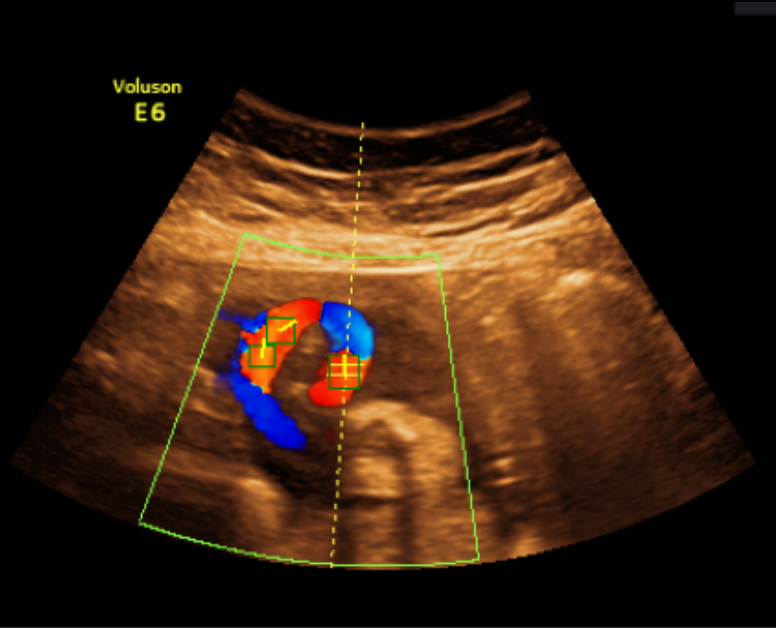

We begin with determining the direction of the ultrasound beam by utilizing the green Doppler box, which becomes active during color Doppler acquisition (see Fig. 3(a)). A binary mask of the green Doppler box is first obtained by color thresholding on the RGB pixels, followed by enhancing the mask using a watershed transform [6]. Next, a Hough line detection algorithm [1] is used to identify the two radial line segments on each side of the box. The ultrasound source is located at the intersection between the two line segments. As an extra step to prevent erroneous detection, we verify that we are able to detect the two arc lines with Hough circle detection when the center location is constrained to be at the intersection point from the previous two Hough lines (see Fig. 3(b)).

(a) Green Doppler box

(b) Detected line (red) and arc (blue)

Figure 3: Locating source of the ultrasound beam by using the green Doppler box.